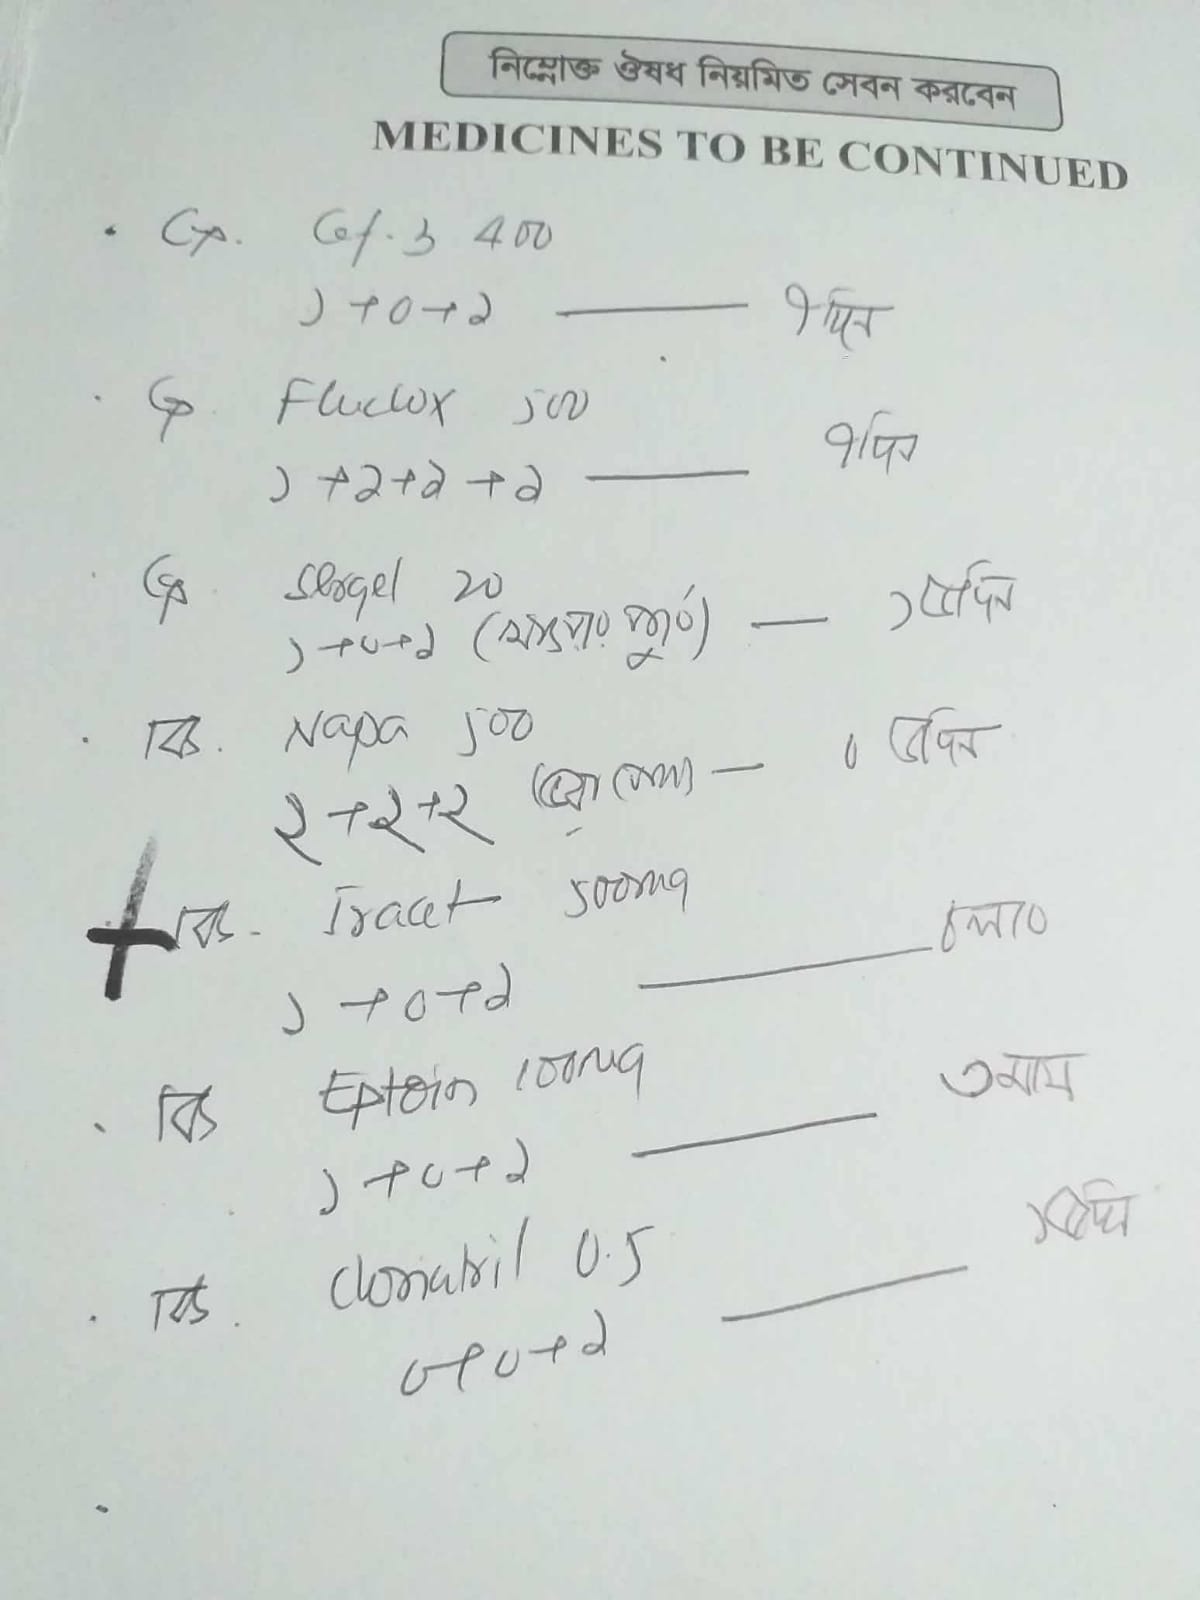

#250909F: দীর্ঘদিন মসজিদের ইমামতি করা জনাব মোতাব্বির হোসেন আজ বিভিন্ন জটিল অসুস্থতায় আক্রান্ত হয়ে সাহায্যের হাত বাড়িয়েছেন। গ্রাম: দক্ষিণ শাঙ্গর, জেলা: হবিগঞ্জ।

মোতাব্বির হোসেন একজন সম্মানিত ইমাম ছিলেন। একসময় তিনি নিয়মিত ইমামতির মাধ্যমে সমাজে ধর্মীয় দায়িত্ব পালন করতেন। কিন্তু বর্তমানে তিনি মারাত্মক শারীরিক অসুস্থতায় ভুগছেন। উনার হা...

Category: Critical Ill Patient

Verification: Online Physical

Received Amount: 500.00 BDT

Contact No: 1726358321